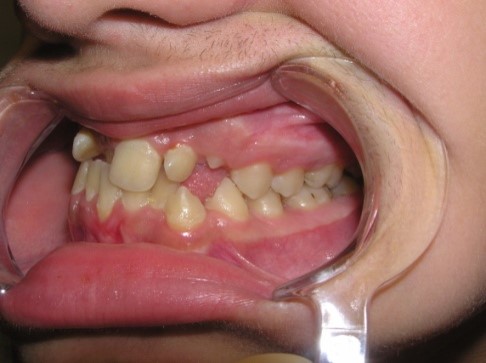

Sysoev N. P. (1975) proposed a

classification of the palatal position of the frontal teeth and identified 4

forms:

Form 1 – palatal position of the

frontal teeth when there is space in the dental arch of the upper jaw. Occurs in

42.4%

Form 2 – palatal position of the

frontal teeth with lack of space in the dental arch as result of the upper jaw

frontal area underdevelopment. Occurs in 29.6%

Form 3 – palatal position of the

frontal teeth, which is combined with protrusion of the lower jaw frontal teeth.

Occurs in 16.89% of cases.

Form 4 – palatal position of the

upper jaw frontal teeth with a lower teeth crowding. Occurs in 11.2%